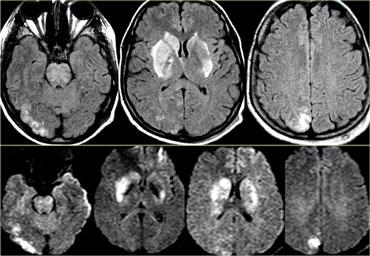

Bên trái là một biến thể khác trong tưới máu não ở bệnh nhân có nhiều ổ nhồi máu được ghi nhận trên hình ảnh khuếch tán (diffusion imaging).

Có một ổ nhồi máu vỏ não nhỏ ở thùy chẩm trái, vùng này được tưới máu bởi động mạch cảnh trong trái (mũi tên).

Lưu ý rằng hệ động mạch đốt sống-nền không tham gia tưới máu cho vùng này.